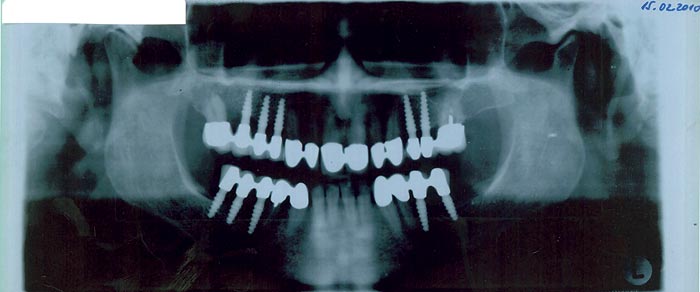

Zaključila sam da nešto moram promijeniti jer ostatak života želim konačno dobro prožvakati hranu. Danas, poslije nešto više od pola godine, mogu se nasmijati od uha do uha, jer imam lijepe zube ili bolje rečeno osjećam se kao da su mi narasli novi.” Sedamdesetgodišnja Vera više je nego zadovoljna sa svojih deset ugrađenih zubnih implantata koji su joj omogućili da se, kako kaže, ponovno osjeća mladom. Zategnulo joj se lice oko usana, popunili obrazi...

Stomatolog dr. Branko Dolenec, koji se dugo bavi i implantologijom, kaže kako se u stomatologiji sve više traži i estetika, ...